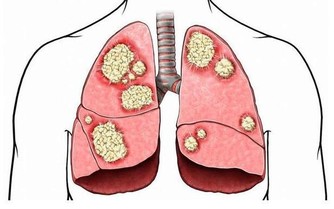

*****標誌5:你的體重在正常範圍內。*****根據臨床研究發現,肥胖和吸煙是腎癌的兩個獨立風險因素,如果你的體重超標,那麼會導致身體出現代謝問題,增加腎病的發生風險。除此之外,你還應該避免吸煙。